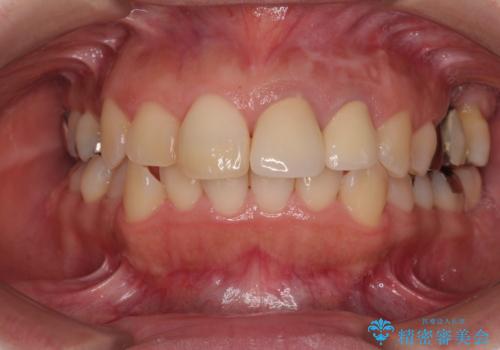

痛みが改善したことを確認した上で、オールセラミッククラウンにて補綴治療を行うこととしました。

歯根端切除から2週間を経過した時点で痛みは全くなくなっており、処置から6ヶ月後に撮影したレントゲン写真では炎症で吸収していた骨が回復している様子が確認されました。